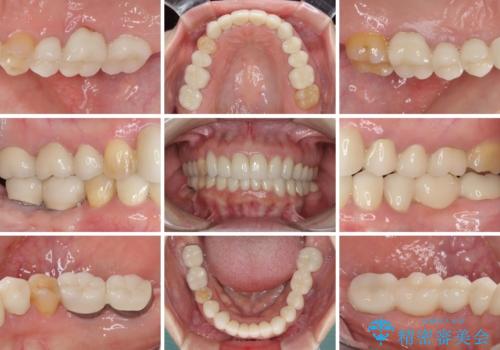

- 下顎の前歯に激痛を覚えて来院された患者様です。

取り急ぎ下顎前歯数歯の根管治療を、銀座しらゆり歯科医院長の林先生にお願いし、それ以外に気になっている、不自然な色調のクラウン、金属部分が見えてブラッシングがしにくいインプラント補綴、口元の突出感、出血のしやすい歯周ポケットなど、全てを解決するための治療を行うこととしました。

期間と費用はかかりましたが、気になっていた部分全てを改善でき、患者様には大変満足していただきました。